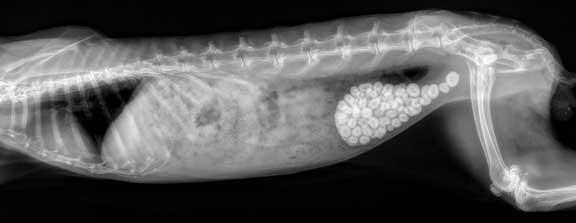

It never hurts to be thorough during this pre-anesthetic exam and take a radiograph (X-ray). The following 3 radiographs, on rabbits that were seemingly normal, show why.

This one has a wee bit more than one stone in its urinary bladder! Click here to learn more about bladder stones in other species.